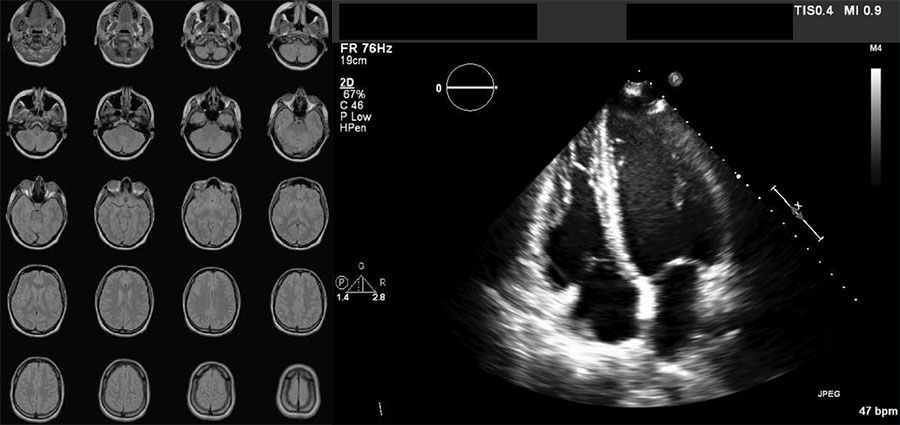

Examples of DICOM-formatted images: a series of 20 images from a brain MRI scan and a cardiac ultrasound image.

MR image series of a brain (left) and a cardiac ultrasound scan (right) stored in DICOM format.